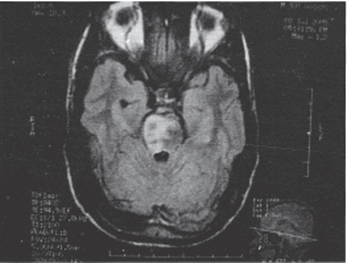

Рисунок 1. T2 Flair МРТ снимок, демонстрирующий билатеральный инфаркт моста (затронувший правую сторону больше, чем левую) (Paliwal et al., 2007)